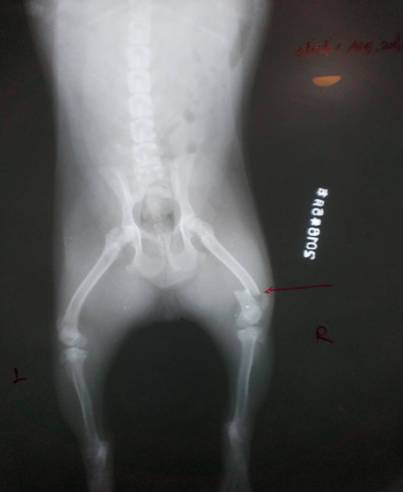

汝陽縣城英斗犬,球球,母,四月齡,右后肢股骨遠端骨折,進行整復手術。

骨折部位X光片顯示病肢股骨遠端橫斷骨折,進行手術治療。